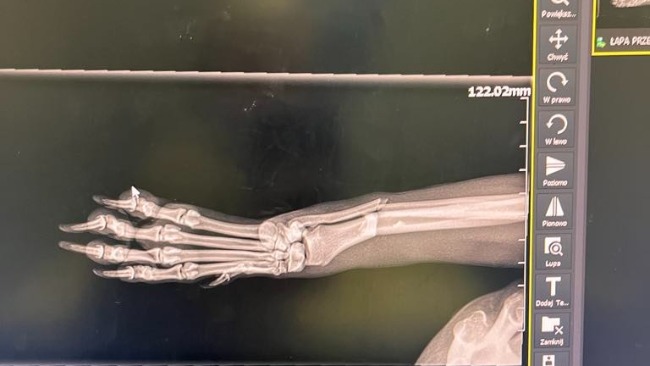

Na chwile obecna ma wstawione w łapkę dwa gwoździe by ustabilizować kości by mogły się zrosnąć .

Jeśli wszystko będzie się ładnie zarastać za około 3 miesiące odbędzie się kolejny zabieg usunięcia tych gwoździ .Tak to wyglada na chwile obecna . Jeszcze raz dziękuje za wszelka pomoc .